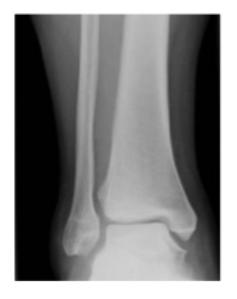

Syndesmotic Injuries

A 17-year-old male had a high ankle sprain followed by pain in his leg. X-ray films were obtained. According to the attached X-ray, which structure has been injured?

- B. Syndesmosis ligament

A 23-year-old male injured his ankle after a twisting ankle injury 2 days back. What is the most likely pathology based on shown x-ray?

Management Question: What is the management of the finding in the image?

- A. Screw fixation for syndesmosis injury